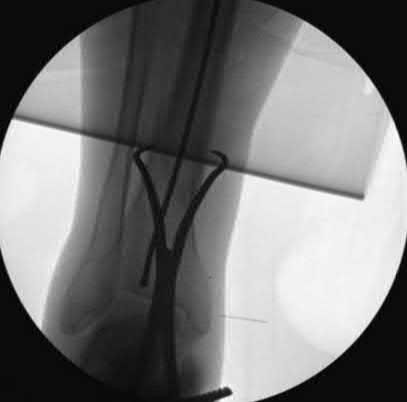

A 25-year-old female is involved in a motor vehicle collision. She presents with the isolated injury seen in Figures A through D. Her leg is swollen but her skin is intact. She has no clinical signs of compartment syndrome. Which of the following treatment options will allow for maintenance of fracture alignment and minimize the risk of soft tissue complications?

The patient presents with a closed distal third metaphyseal-diaphyseal distal tibia fracture with simple intra-articular extension. Immediate intramedullary nailing along with percutaneous fixation of the articular component provides appropriate restoration of length, rotation and alignment and minimizes the risk of wound complication.

Displaced distal third tibia fractures may be associated with simple intraarticular extension. Operative treatment of intra-articular distal tibia fractures has historically been performed with open reduction and internal fixation. Early open reduction and plate fixation of pilon fractures has been associated with high rates of infection and wound complication. In select patterns with simple articular extension, percutaneous screw fixation and medullary nailing may provide appropriate reduction with minimal soft-tissue risk.

Figures A and B demonstrate a distal third tibial shaft fracture with simple intra-articular extension. The axial and coronal CT cuts in Figures C and D further clarify the articular injury. Illustrations A and B demonstrate a comminuted distal third tibial fracture with simple intra-articular extension. Illustrations C and D are fluoroscopic images of the same injury after intramedullary nailing and percutaneous fixation of the articular component.